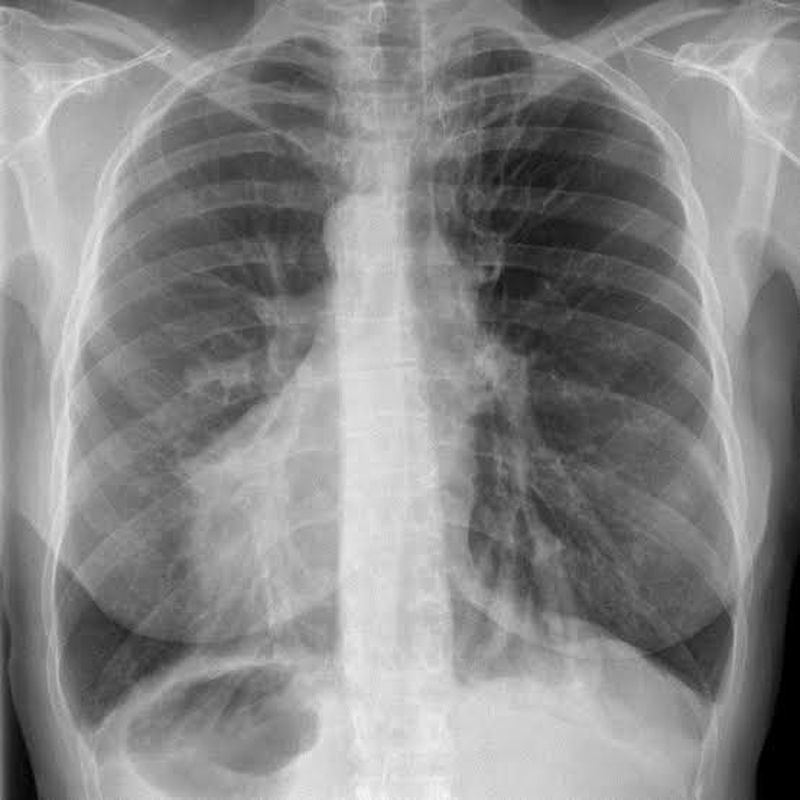

also there was this time when some one asked me why the right crus of diaphram is higher than the left.....confidently i said.. because there is the liver....he confidenlty replied back WRONG.....later i found out that its becoz the heart pushes the left crus down...why?becoz in cases of situs inversus and dextrocardias...the right crus lies lower..as seen in the x ray posted

many years ago a guy named seiwert found a case with situs inversus ,sinusitis and brochiectasis ..later kartagener named the triad ..kartageners syndrome (primart immotile cilia syndrome)...anatomically and physiologically the ear , respiratory , sinus problems are relatable..